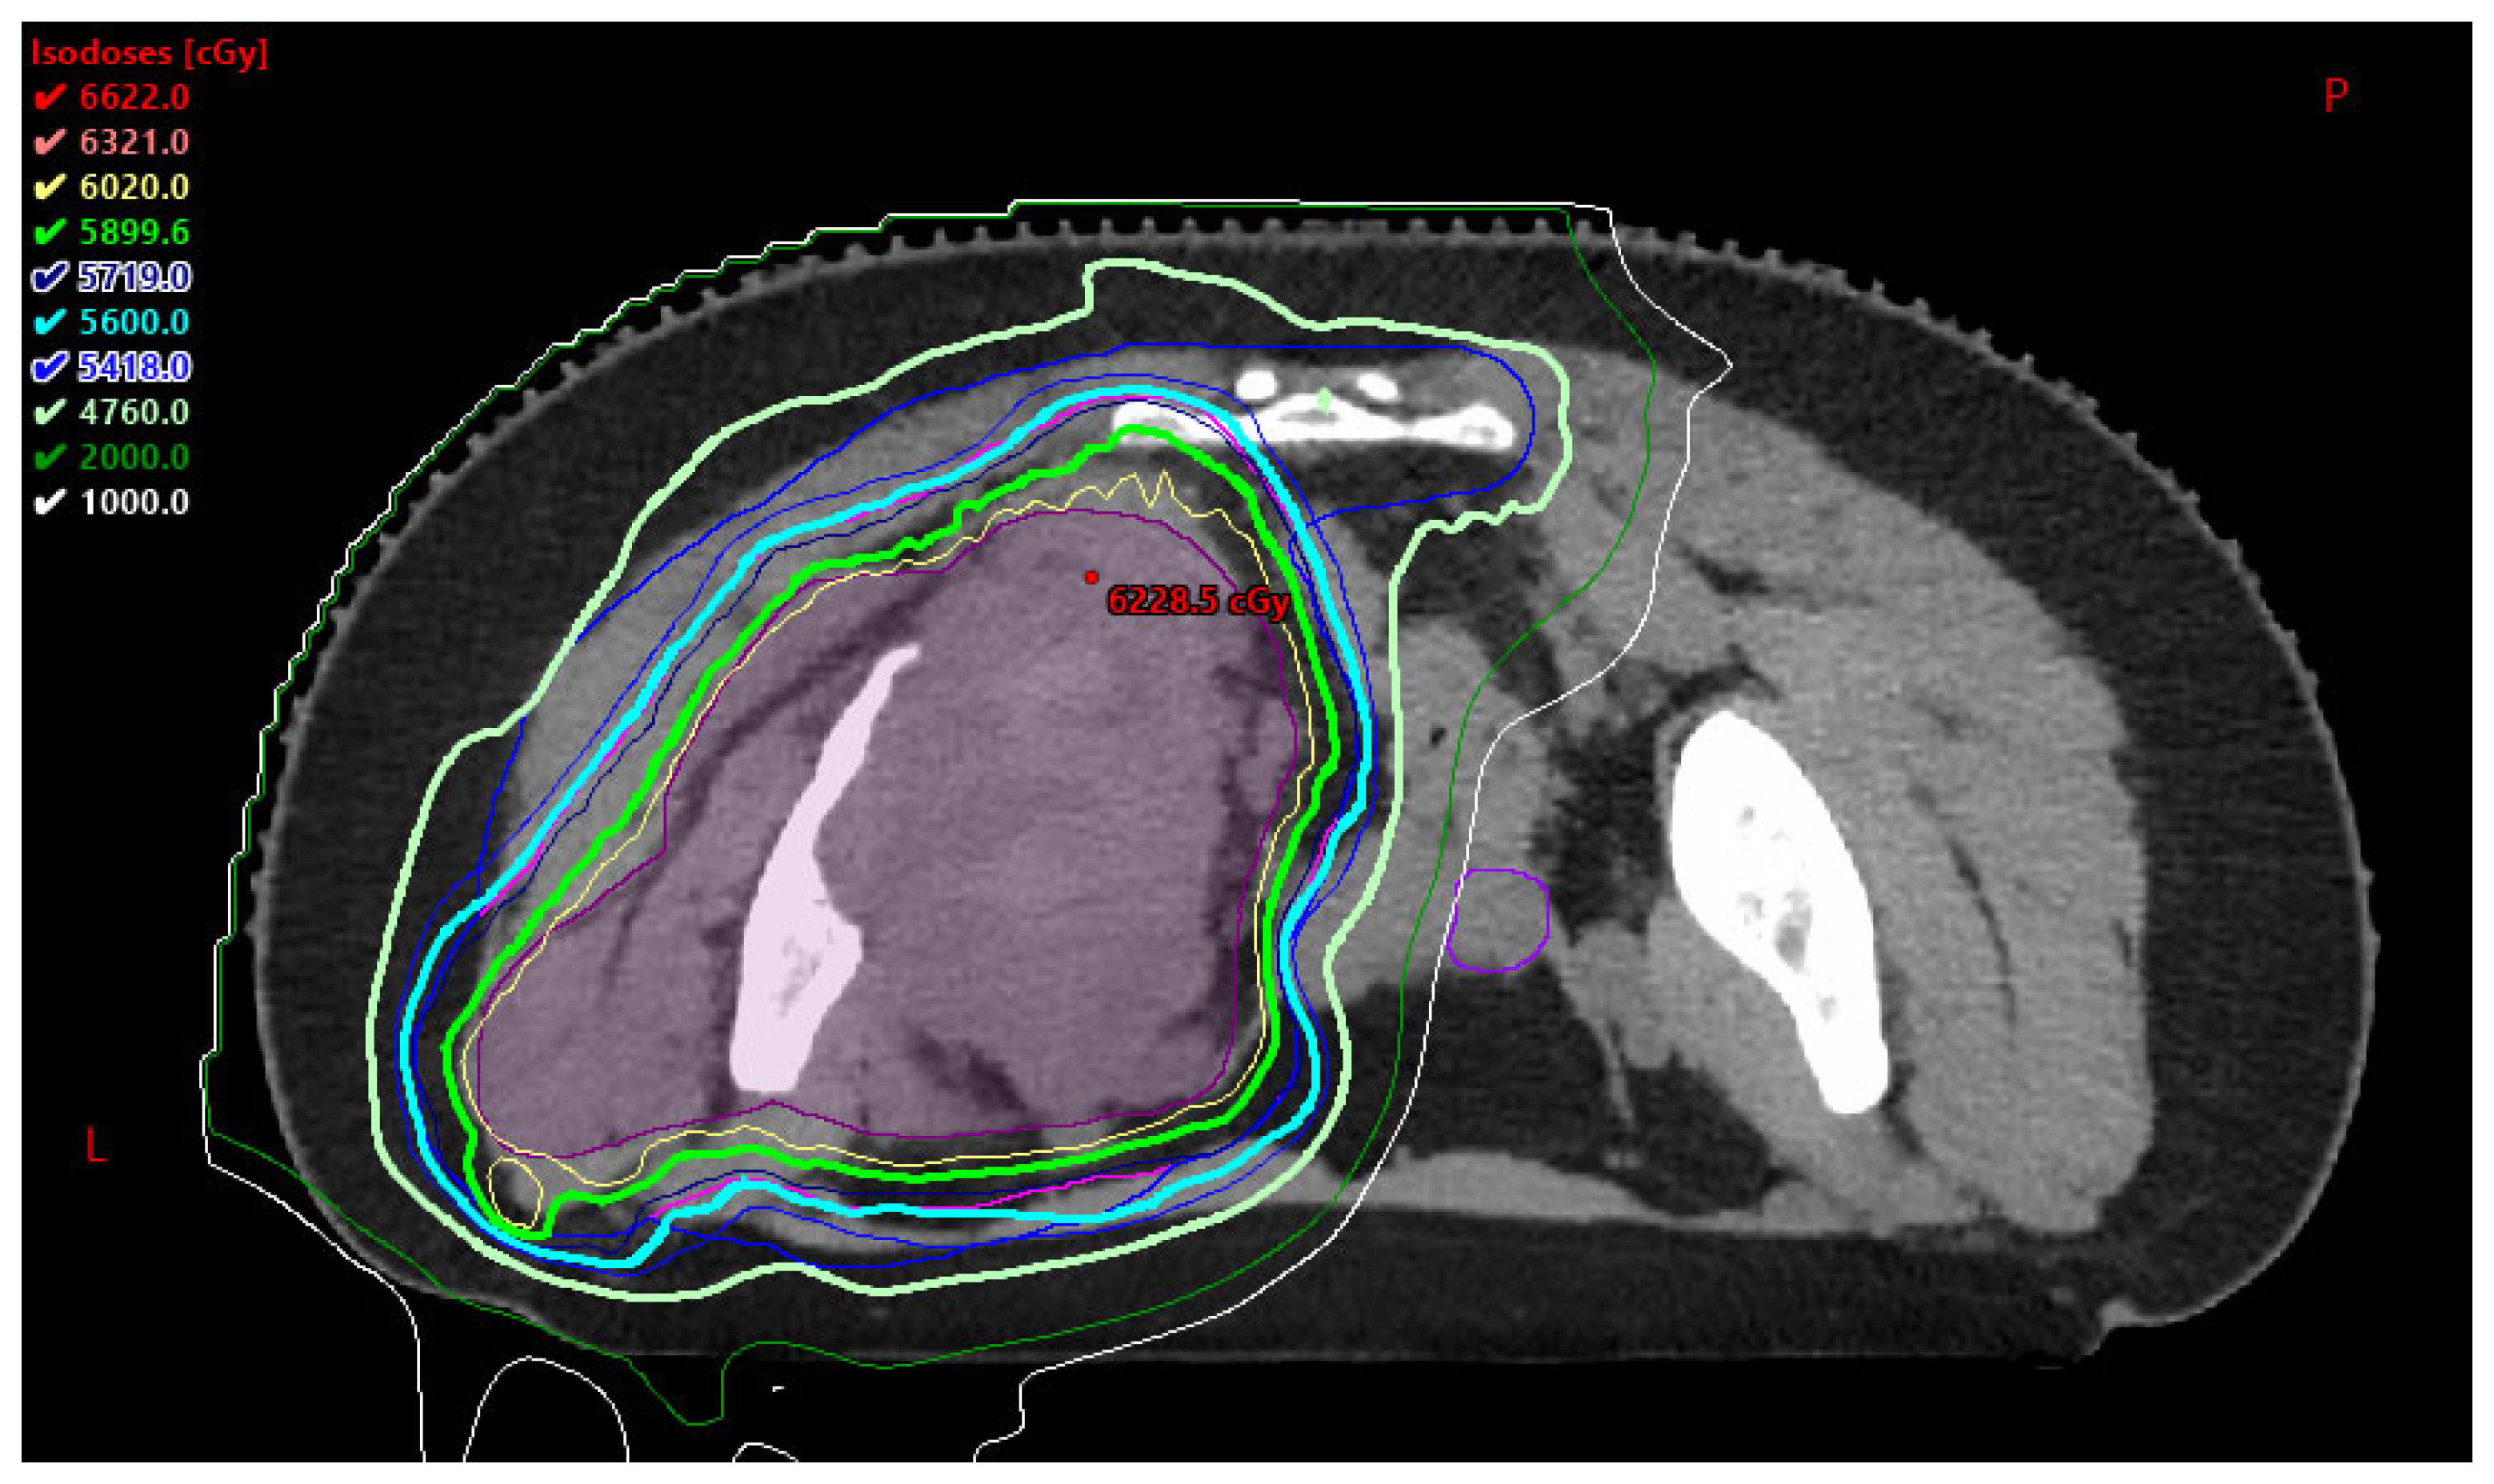

3.2.1. Benefits to PBT